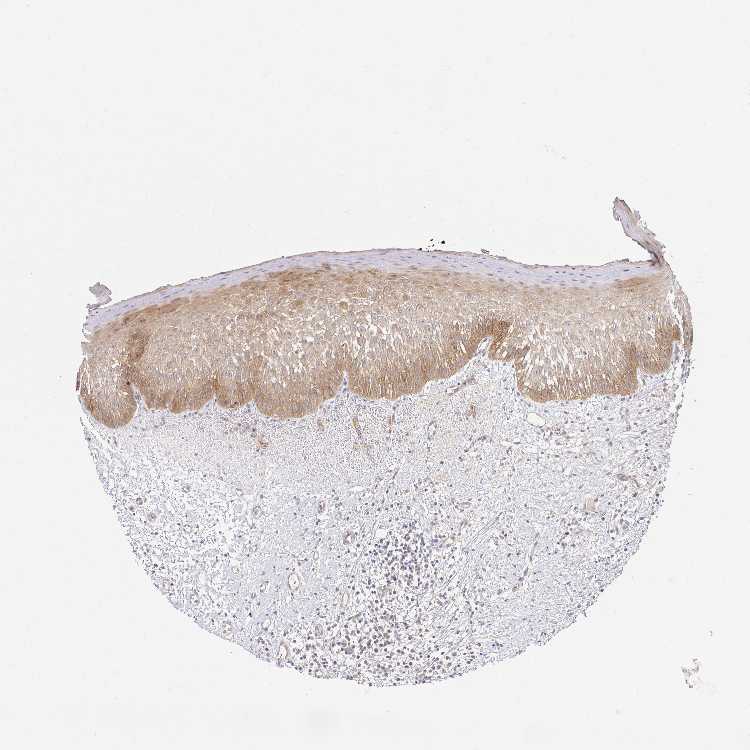

TISSUE PRIMARY DATA ORAL MUCOSA Show tissue menu

Oral mucosa

ORAL MUCOSA - Antibody stainingi

Antibody staining in the annotated cell types in the current human tissue is reported as not detected, low, medium, or high, based on conventional immunohistochemistry profiling in selected tissues. This score is based on the combination of the staining intensity and fraction of stained cells.

Each image is clickable and will lead to virtual microscopy that enables deeper exploration of all samples and also displays staining intensity scores, fraction scores and subcellular localization as well as patient and tissue information for each sample.

Antibody HPA060991Antibody HPA063556Antibody CAB017690

Squamous epithelial cells MediumMediumMedium